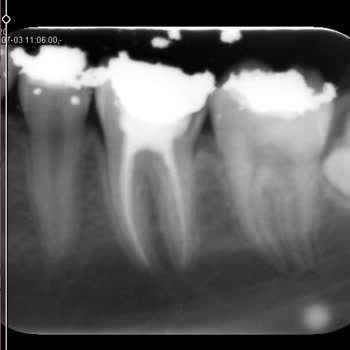

İzmir Alsancak ADSM’de yaklaşık 1,5 yıl önce DT. G***** S******* tarafından aynı gün içinde, toplamda sadece 20 dakika gibi kısa bir sürede bir kanal tedavisi ve iki dolgu işlemi yapıldı. Tıbbi standartlara göre çok daha uzun sürmesi gereken bu işlemlerin bu kadar süratle bitirilmesi, 1,5 yıldır sür...